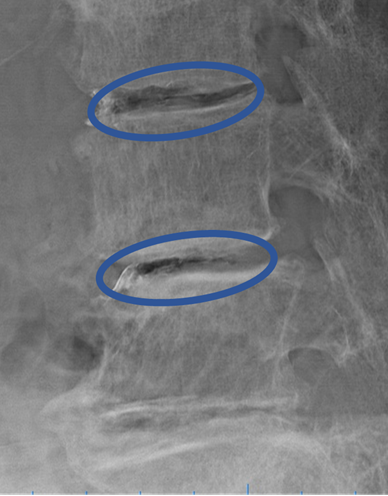

患者様と相談の元、 L3/4、4/5 にセルゲル法を施行

DiscoGelを入れた後の画像になります。

治療は 30分程度で終了

回復室で休憩後、歩いて帰院されました。